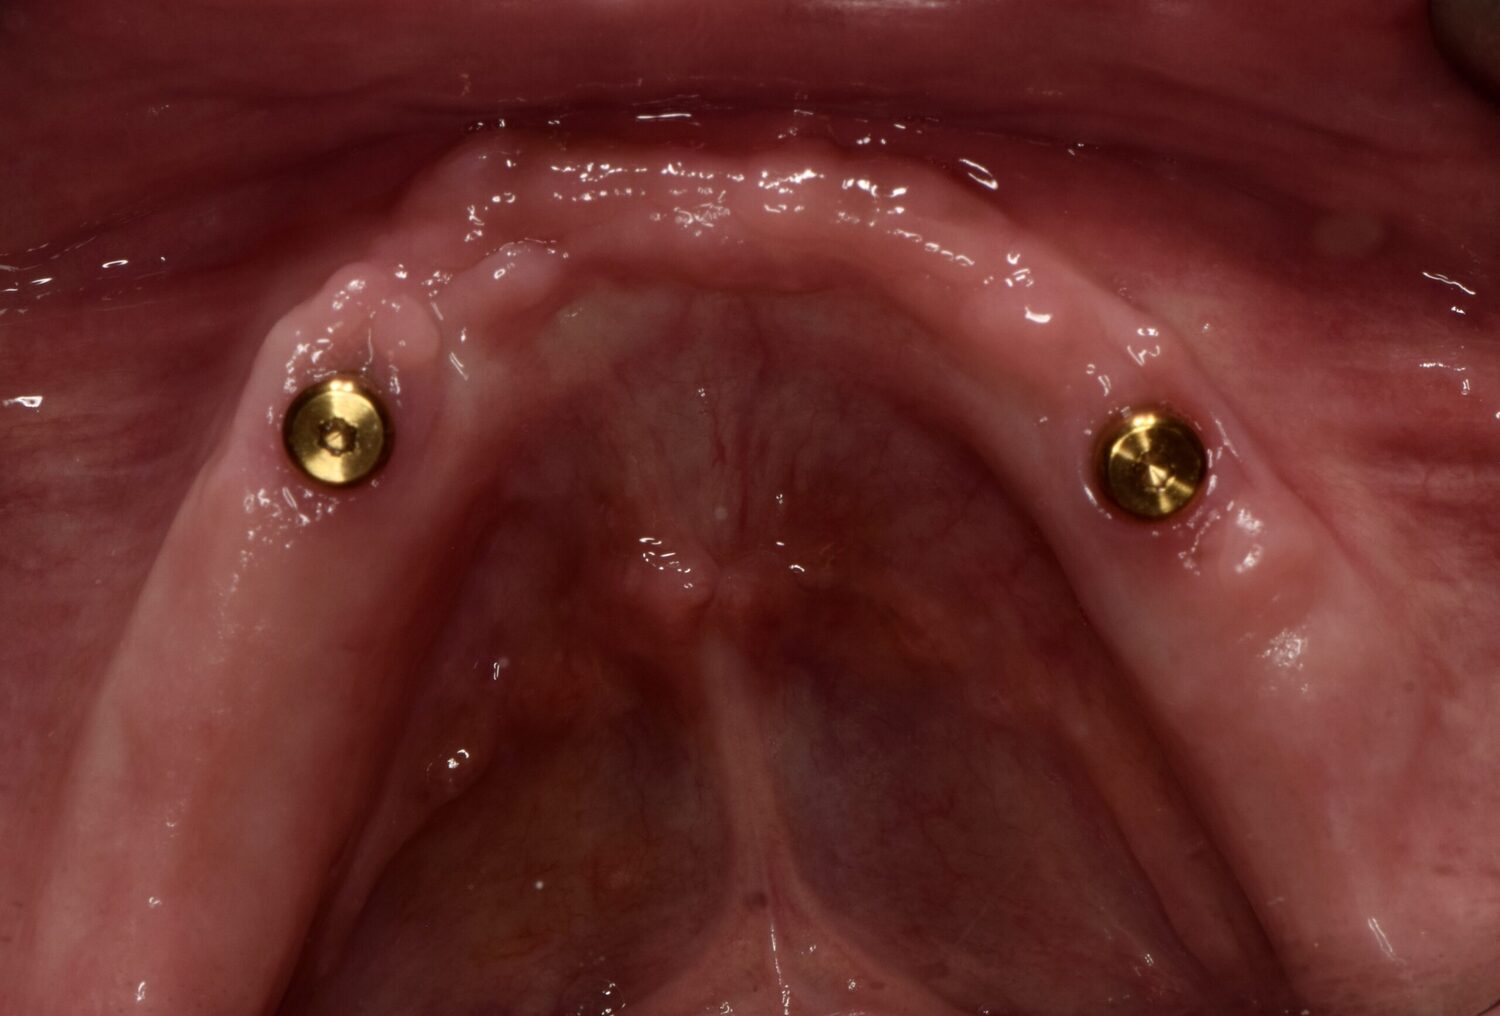

Our Belmont implant-supported dentures anchor directly to dental implants, creating a secure fit that doesn’t shift or slip. Whether you’re replacing a full arch or multiple teeth, we’re committed to delivering a result that feels natural and gives you the freedom to eat, speak, and smile with ease.

Implant dentures are locked in place using dental implants, eliminating the movement and irritation common with traditional dentures.

No — our Belmont implant-supported dentures typically require just a few implants per arch to support a full set of replacement teeth securely.